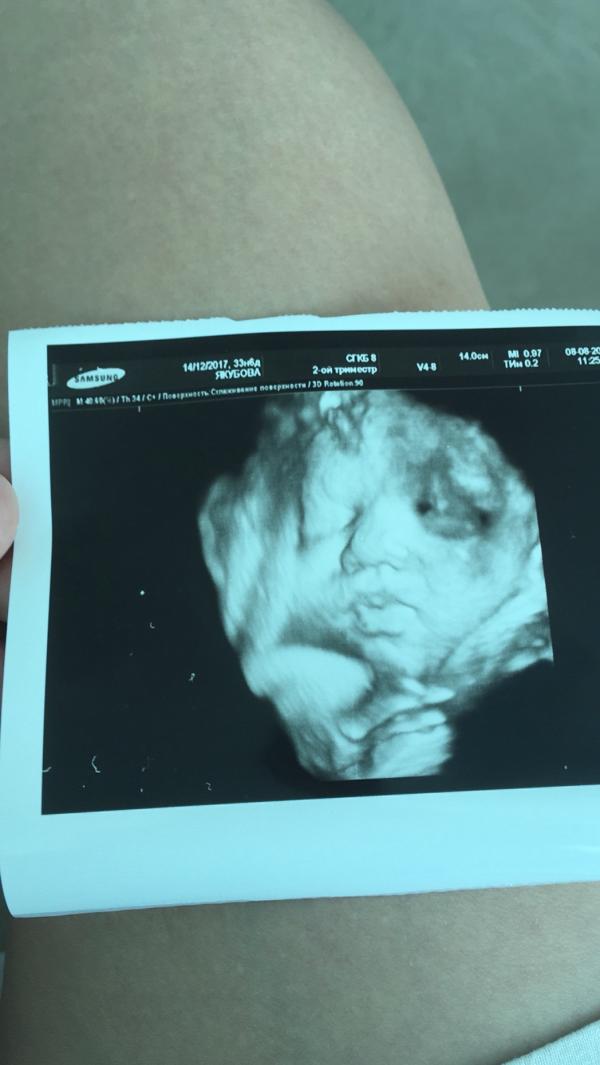

На УЗИ перед выпиской сделали фотографию моей малютки) уж никак не ожидала, что при скрещивании меня и мужа получится... копия моей мамы! 😂 мы в полном шоке! Сама я похожа на своего отца, ни капли от мамы не унаследовала, а моя дочь вылитая она, как так произошло?!😁

@tobolevak, спасибо Вам!))) даа, губы- слава Богу не мои, я так переживала) у нас и папа губастый , а вообще не важно на кого похожи детки, главное чтобы здоровые! 🌺

@viktorija-yakubova17 свекровь верно говорит) какой сын был первый месяц жизни и какой сейчас-два разных человека) а по фото правда, красотка там сидит, невероятная!) Губы одни чего только стоят.)

Какие губехи😍 ттт